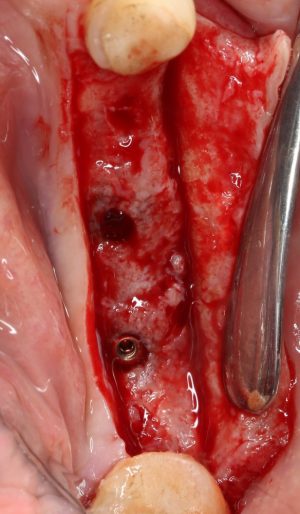

Рекомендации по установке имплантов. Для всех. Часть III